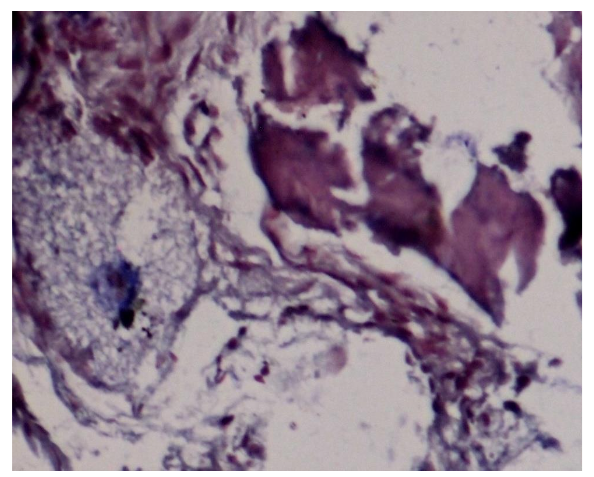

Biopsies were fixed in 10% formalin, decalcified with 0.5M EDTA, and sectioned. Hematoxylin and eosin (HE), Van Geison, Mason trichrome and Picrosirius Red were used. Microscopic analysis revealed remnants of dentin particles integrated with new lamellar bone. Plump osteoblasts, entrapped osteocytes, and fibrovascular stroma with minimal chronic inflammation were evident, confirming osteoconductive and osteoinductive potential. Mature bone trabeculae along with residul graft material were confirmed with various special stains.